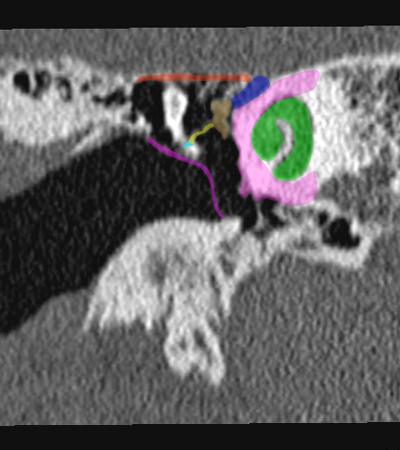

Coupe axiale passant par le canal semi-circulaire supérieur Coupe axiale passant par le canal semi-circulaire latéral Coupe axiale passant par le modiolus de la cochlée Coupe axiale passant par la fenêtre ronde Coupe axiale passant par le ganglion géniculé Coupe axiale passant par l'articulation incudo-malléaire Coupe axiale passant par la partie pétreuse de l'artère carotide interne Coupe axiale passant par le nerf tympanique

Coupe axiale passant par le foramen styloïde Coupe coronale passant par le muscle tenseur du tympan Coupe coronale passant par le recessus epitympanique Coupe sagittale passant par le segment mastoïdien du nerf facial coupe sagitalle oblique passant par le canal semi-circulaire supérieur (plan de Pöschl) Reconstruction axiale passant par le plan de l'étrier Coupe axiale passant par les apex pétreux